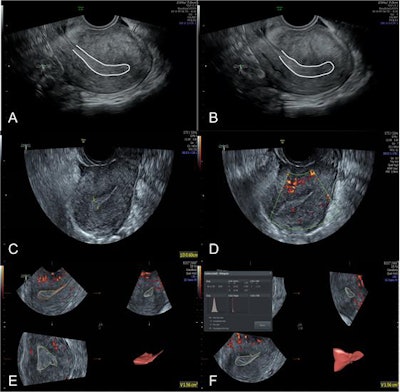

The first study aimed to determine the value and feasibility of ultrasound multimodal scoring for evaluating endometrial receptivity in patients with artificial abortion. This technique can be used to assess some endometrium-related factors, such as endometrial morphology, blood flow, and peristaltic waves, Jiao and colleagues explained.

Sixty-eight patients who had had an artificial abortion (AA group) and 70 women of childbearing age without any history of abortion (control group) were recruited between January 2018 and December 2018. All subjects received the examination of endometrium in the middle luteal phase (7-9 days after ovulation) with 2D grayscale ultrasound, 2D color Doppler ultrasound, and 3D ultrasound, and the quantitative scores were obtained and compared between the two groups.

The quantitative score of endometrial receptivity was 10.46 ± 2.99 in the AA group and 13.49 ± 2.21 in the control group, showing a significant difference (p < 0.05), the authors stated.